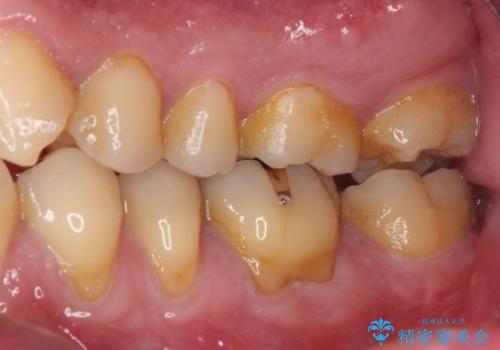

後方は歯肉内にまで虫歯が及んでいたため、歯肉の一部を切除して、クラウンとの境目を明示して処置を行いました。

クラウン装着後には、来院時に気になさっていた歯肉の腫れが解決され、快適に生活を送れるようになりました。